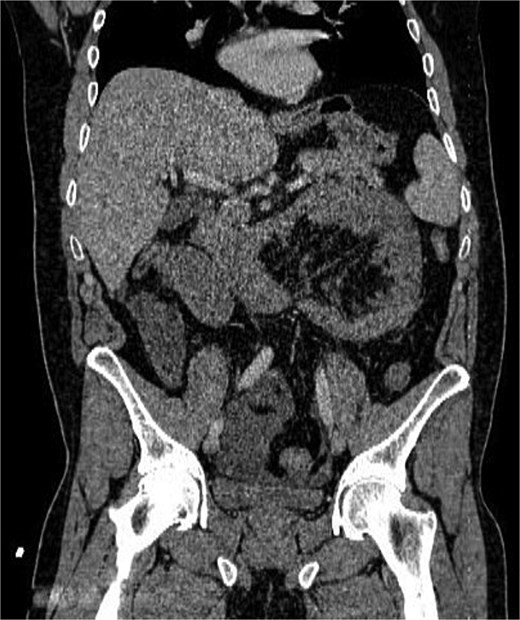

أظهرت الفحوصات والتصوير الطبي وجود فتق داخلي نادر أدى إلى احتباس جزء من الأمعاء الدقيقة داخل تجويف غير طبيعي في البطن، ما تسبب في انسدادها وانقطاع التروية الدموية عنها.

ويُعد هذا النوع من الحالات من الأسباب النادرة لانسداد الأمعاء، لكنه قد يتحول بسرعة إلى حالة مهددة للحياة إذا لم يتم التدخل الجراحي العاجل.

وخلال العملية اكتشف الأطباء أن جزءًا من الأمعاء الدقيقة تعرض للاختناق والتلف نتيجة الفتق الداخلي.

وقام الفريق الجراحي باستئصال نحو 60 سنتيمترًا من الجزء المتضرر من الأمعاء، ثم إعادة توصيل الأمعاء السليمة جراحيًا، مع معالجة سبب الفتق بشكل كامل.